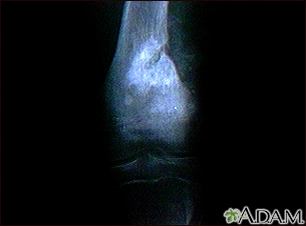

Osteogenic sarcoma - x-rayBackOsteogenic sarcoma - x-rayThis x-ray shows a malignant bone tumor (osteogenic sarcoma) of the knee. This type of tumor is usually seen in adolescents (around 15 years old). This tumor extends from the bone into the surrounding tissue. E-mail FormEmail ResultsName:Email address:Recipients Name:Recipients address:Message: